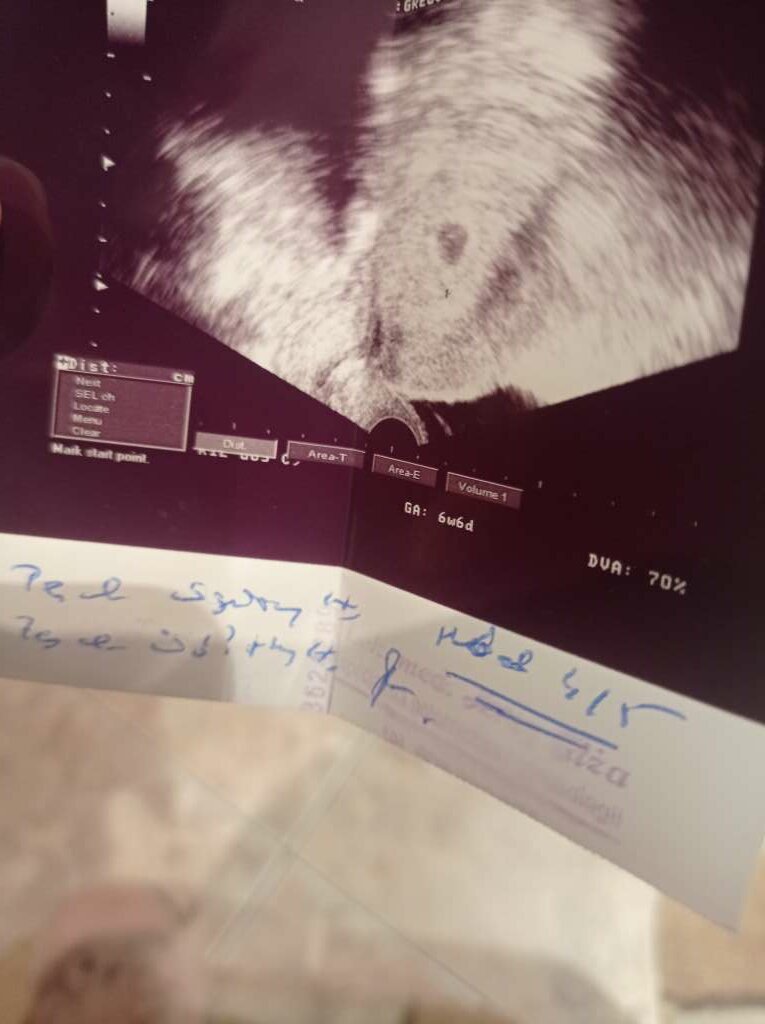

nie robilam juz bety u mnie w ogole jakos dziwnie. Bo poszlam do lekarza pierwszego rosno 5 tygodni po @. Powiedzial ze nuby to 2/3 tydzien ciazy bylo widac pecherzych. Kazal przyjsc za dwa tygodnie i wtedy powiedzial ze to 4/5 tydzien jest cialko zolte nie ma zarodka. Wystraszylam sie na drugi dzien poszlam do kolejnego i powiedzial ze to 5 tydzien i 1 dzien i jest zarodek. I tak kolejno wyszly zdjecia usg od 2 lekarzy.A beta na jakim poziomie? Z ciekawości spytam. Bo do wizyty u lekarza prawie tydzień a nie mogę się doliczyć Bo z bety wychodzi mi że 6 tydz. Z miesiączki że 4/5 mc

Może ma znaczenie dobra aparatura i umiejętnośc szukanianie robilam juz bety u mnie w ogole jakos dziwnie. Bo poszlam do lekarza pierwszego rosno 5 tygodni po @. Powiedzial ze nuby to 2/3 tydzien ciazy bylo widac pecherzych. Kazal przyjsc za dwa tygodnie i wtedy powiedzial ze to 4/5 tydzien jest cialko zolte nie ma zarodka. Wystraszylam sie na drugi dzien poszlam do kolejnego i powiedzial ze to 5 tydzien i 1 dzien i jest zarodek. I tak kolejno wyszly zdjecia usg od 2 lekarzy.

bardzo mozliwe heheh zobaczymy za dwa tygodnie bo powinnam.miec zalozona karte ciazyMoże ma znaczenie dobra aparatura i umiejętnośc szukania![]()